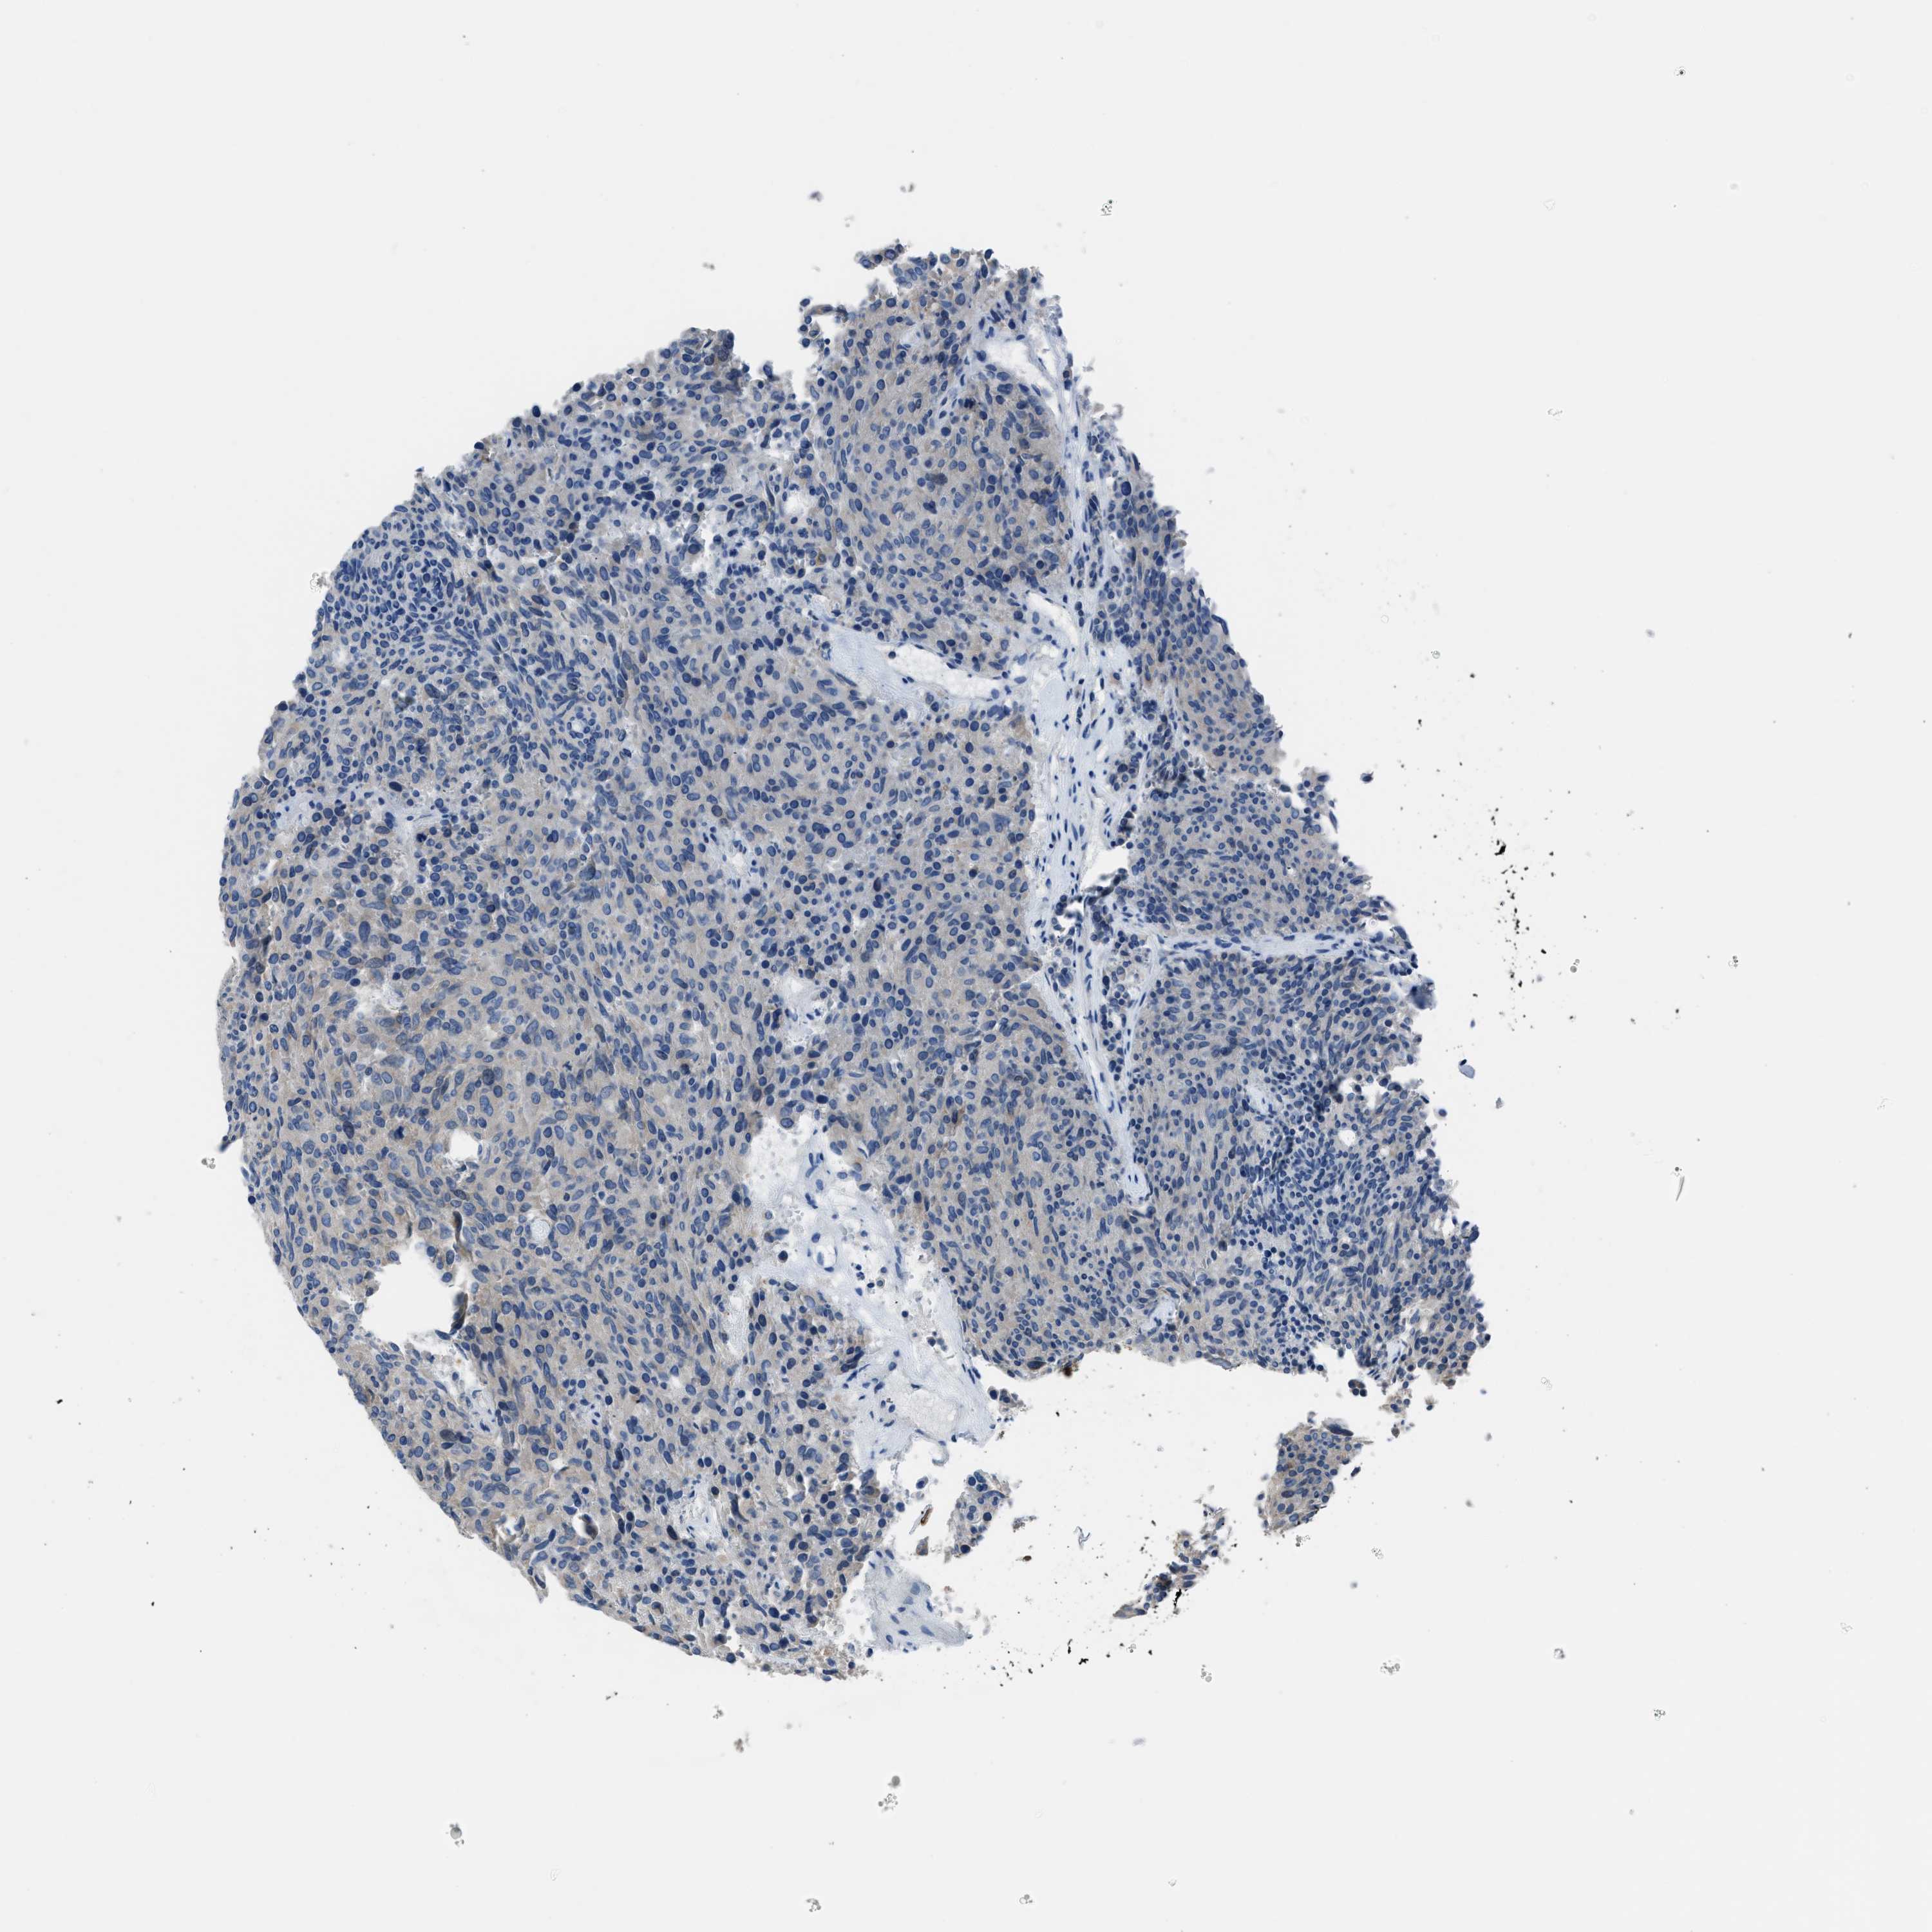

CARCINOID - Protein expressioni

A mouse-over function shows sample information and annotation data. Click on an image to view it in a full screen mode. Samples can be filtered based on level of antibody staining by selecting one or several of the following categories: high, medium, low and not detected. The assay and annotation is described here.

Antibody stainingi

Antibody staining in the annotated cell types in the current human tissue is reported as not detected, low, medium, or high, based on conventional immunohistochemistry profiling in selected tissues. This score is based on the combination of the staining intensity and fraction of stained cells.

Each image is clickable and will lead to virtual microscopy that enables deeper exploration of all samples and also displays staining intensity scores, fraction scores and subcellular localization as well as patient and tissue information for each sample.

Antibody HPA016552

Staining

High

Medium

Low

Not detected

Intensity

Strong

Moderate

Weak

Negative

Quantity

>75%

75%-25%

<25%

None

Location

Nuclear

Cytoplasmic/membranous

Cytoplasmic/membranous,nuclear

Carcinoid, malignant, NOS

Carcinoma, NOS